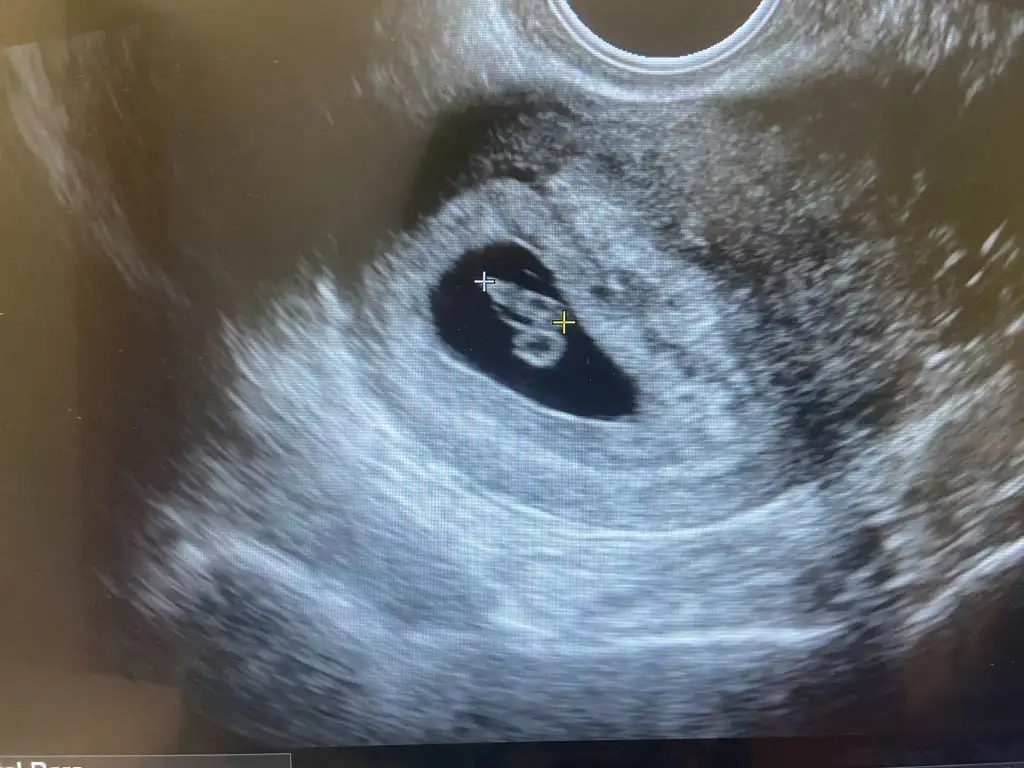

Ay maşallah bence erkek :) hatta baya net belli, vajinal olduğu için sağdaysa erkek oluyormuş. Ama en iyiCinsiyet tahmini yapan var mı aramızdaaa

Hanımlarrrr 11+3tük dün yerimizde durmuyoruz öyle hareketliyiz ki kalp atışını tam dinliyoruz hopp ayaklarıyla kendini yukarı çekip aşağıya kayıyoruz ya da zıplıyoruz asla annemize kalp atışımızı dinletemedi yaramaz